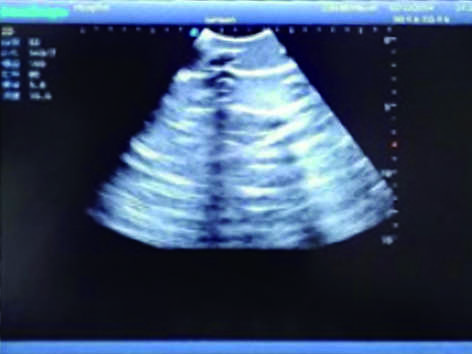

3)  Showing clear and real images of the tissues and organs (including muscle and connective tissue, air-containing lung tissue, pleural structure)

5)  Fluid in the chest to simulate pleural effusion

6)  Pneumothorax to release gas pressure